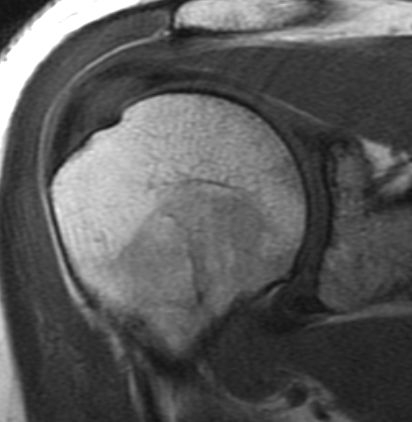

What is being demonstrated on this T1W image?

The image demonstrates high signal within the supraspinatus tendon.

If on the T2 image the signal becomes brighter then this represents tendinitis (aka tendinosis) or a partial tear.

if on the T2 image the signal does not increase in intensity then this is normal may just represent myxoid degeneration